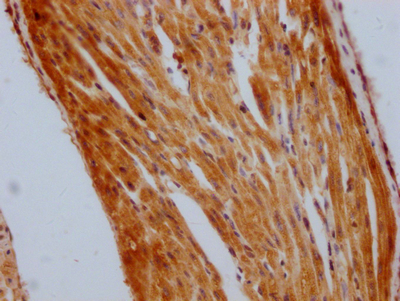

DescriptionSTAT3 Recombinant Monoclonal Antibody [3A9]. Unconjugated. Raised in: HEK293F Cell.

ApplicationELISA, WB, IHC; Recommended dilution: WB:1:500-1:5000, IHC:1:50-1:200